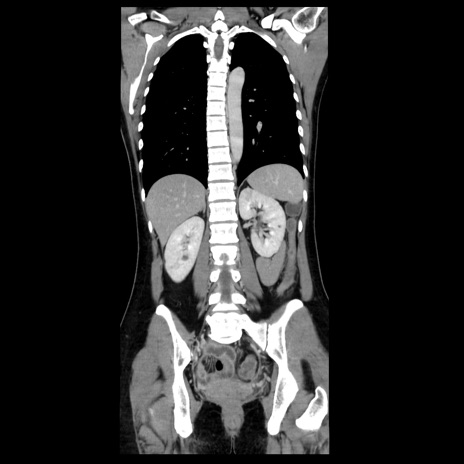

症例39(冠状断像)

CT